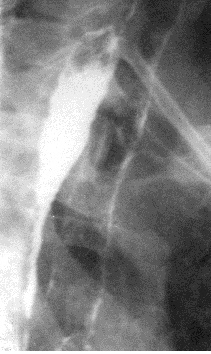

Различают два вида изменений внутренних органов при рентгенографии без применения контрастного вещества. Первый вариант - весь орган или отдельные его части становятся на рентгеноскопическом экране менее прозрачными и вроде затемненными (симптом затемнения), второй – наоборот, орган или отдельные части выглядят более прозрачными (симптом просветления). Рентгенограмма по отношению к изображению на рентгеноскопическом экране, является негативом. Поэтому светлым участкам на экране соответствуют темные на пленке (просветления, рис 2), и наоборот, темним участкам – светлые (тени, рис.3).

Распространенное просветление встречается при пневмотораксе (рис 2). При этом, как правило, в медиальных отделах видим коллабированное легкое, смещение средостения в противоположный бок, а размещение газа не соответствует долевому строению легкого.